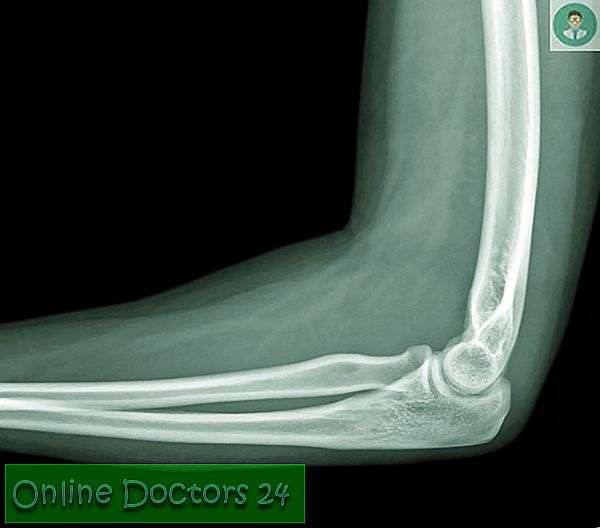

Запитання 19

РОЗПІЗНАЙТЕ КІСТКУ. ПЕРЕЛОМ ЯКОЇ ЇЇ ЧАСТИНИ ВИ БАЧИТЕ НА РЕНТГЕНОГРАМІ?

варіанти відповідей

ULNA

RADIUS

FEMUR, ШИЙКА

ПРОКСИМАЛЬНОГО ЕПІФІЗА

ДИСТАЛЬНОГО ЕПІФІЗА

ДІАФІЗА

ЛІКТЬОВОГО ВІДРОСТКА

ПРОМЕНЕВОГО ВІДРОСТКА